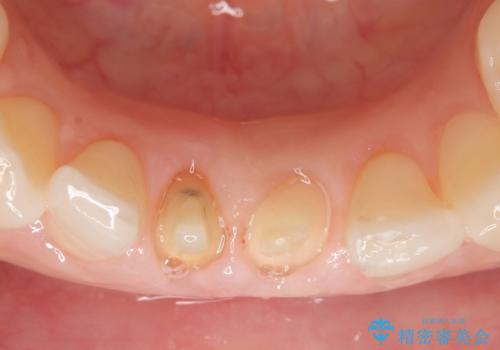

- 下顎前歯の見た目が気になるといらっしゃった方の症例です。

右下1の再根管治療終了後、オールセラミッククラウン(スペシャル)による補綴を行いました。